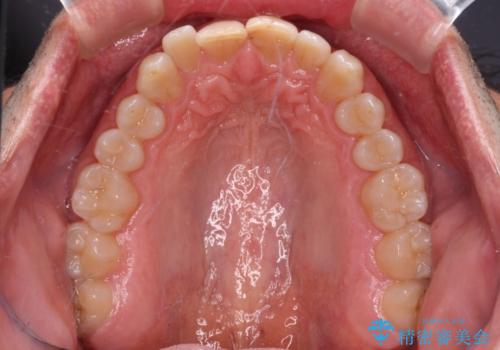

- 前歯のデコボコを気にして来院された患者様です。

インビザラインでもワイヤー装置でも対応可能でしたが、仕事の都合で来院回数を減らしたいとのことでインビザラインによる矯正治療を選択されました。

著しく咬合力が強いため、奥歯がしっかりと噛めずに治療が長引くことが懸念されました。

1セット目のインビザラインを使用した際には左右ともに大臼歯が咬み合っていなかったのですが、2セット目できっちりと仕上げることができました。